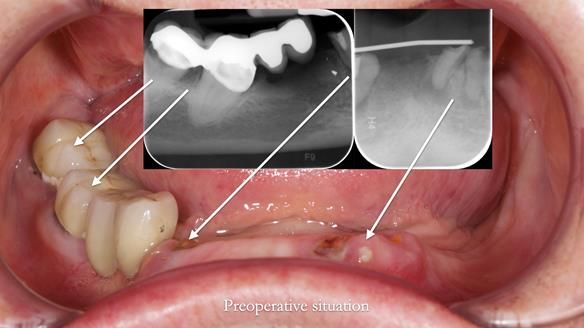

Mary was referred to me by her cousin, who is a dentist. She wanted help with new dentures but made it clear from the start that she didn’t want dental implants. She’d heard about previous implant failures and was already very comfortable wearing dentures. Her neuromuscular control was excellent.

- Extraction of lower 32, 33, 47 and 43

The original plan was to finish the lower as a conventional metal-based partial denture, as shown in the initial design below.